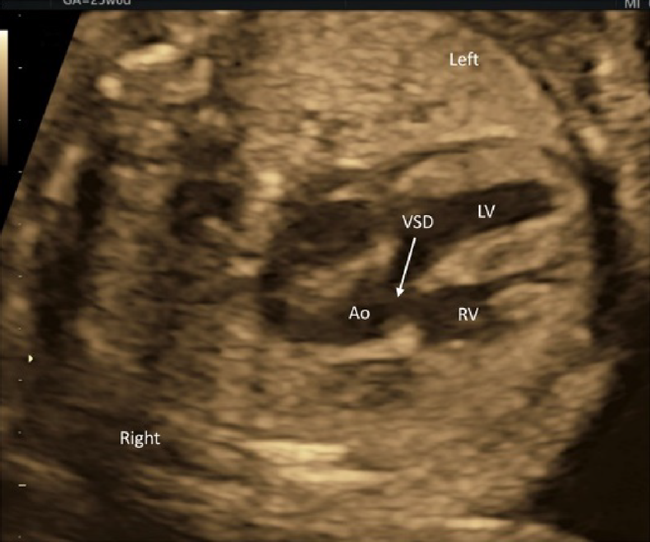

(3) Observation of the Outflow Tracts

The left ventricular outflow tract can be visualized by tilting the probe cranially from the 4CV position. Further tilting demonstrates the right ventricular outflow tract. These outflow tracts typically form a crossover spiral, with the left ventricular outflow tract going from left to right, and the right going from right to left. Further tilting of the probe reveals the bifurcation of the left and the right pulmonary arteries. This view confirms the pulmonary arterial trunk and the aorta originate from the right and the left ventricles, respectively. Abnormal positions and relationship of these structures would imply transposition of the great arteries or double outlet right ventricle. The outflow tracts in these diseases may better be understood by rotating the probe.

The morphology of the ventricular septum at the outflow tracts and defects there, if any, are visualized on a view for the left ventricular outflow tract. A blood flow pattern across the outflow tracts can be observed using color Doppler ultrasound. If a color change or a mosaic pattern is detected at the valve level, the flow rate can be assessed using pulsed Doppler ultrasound.